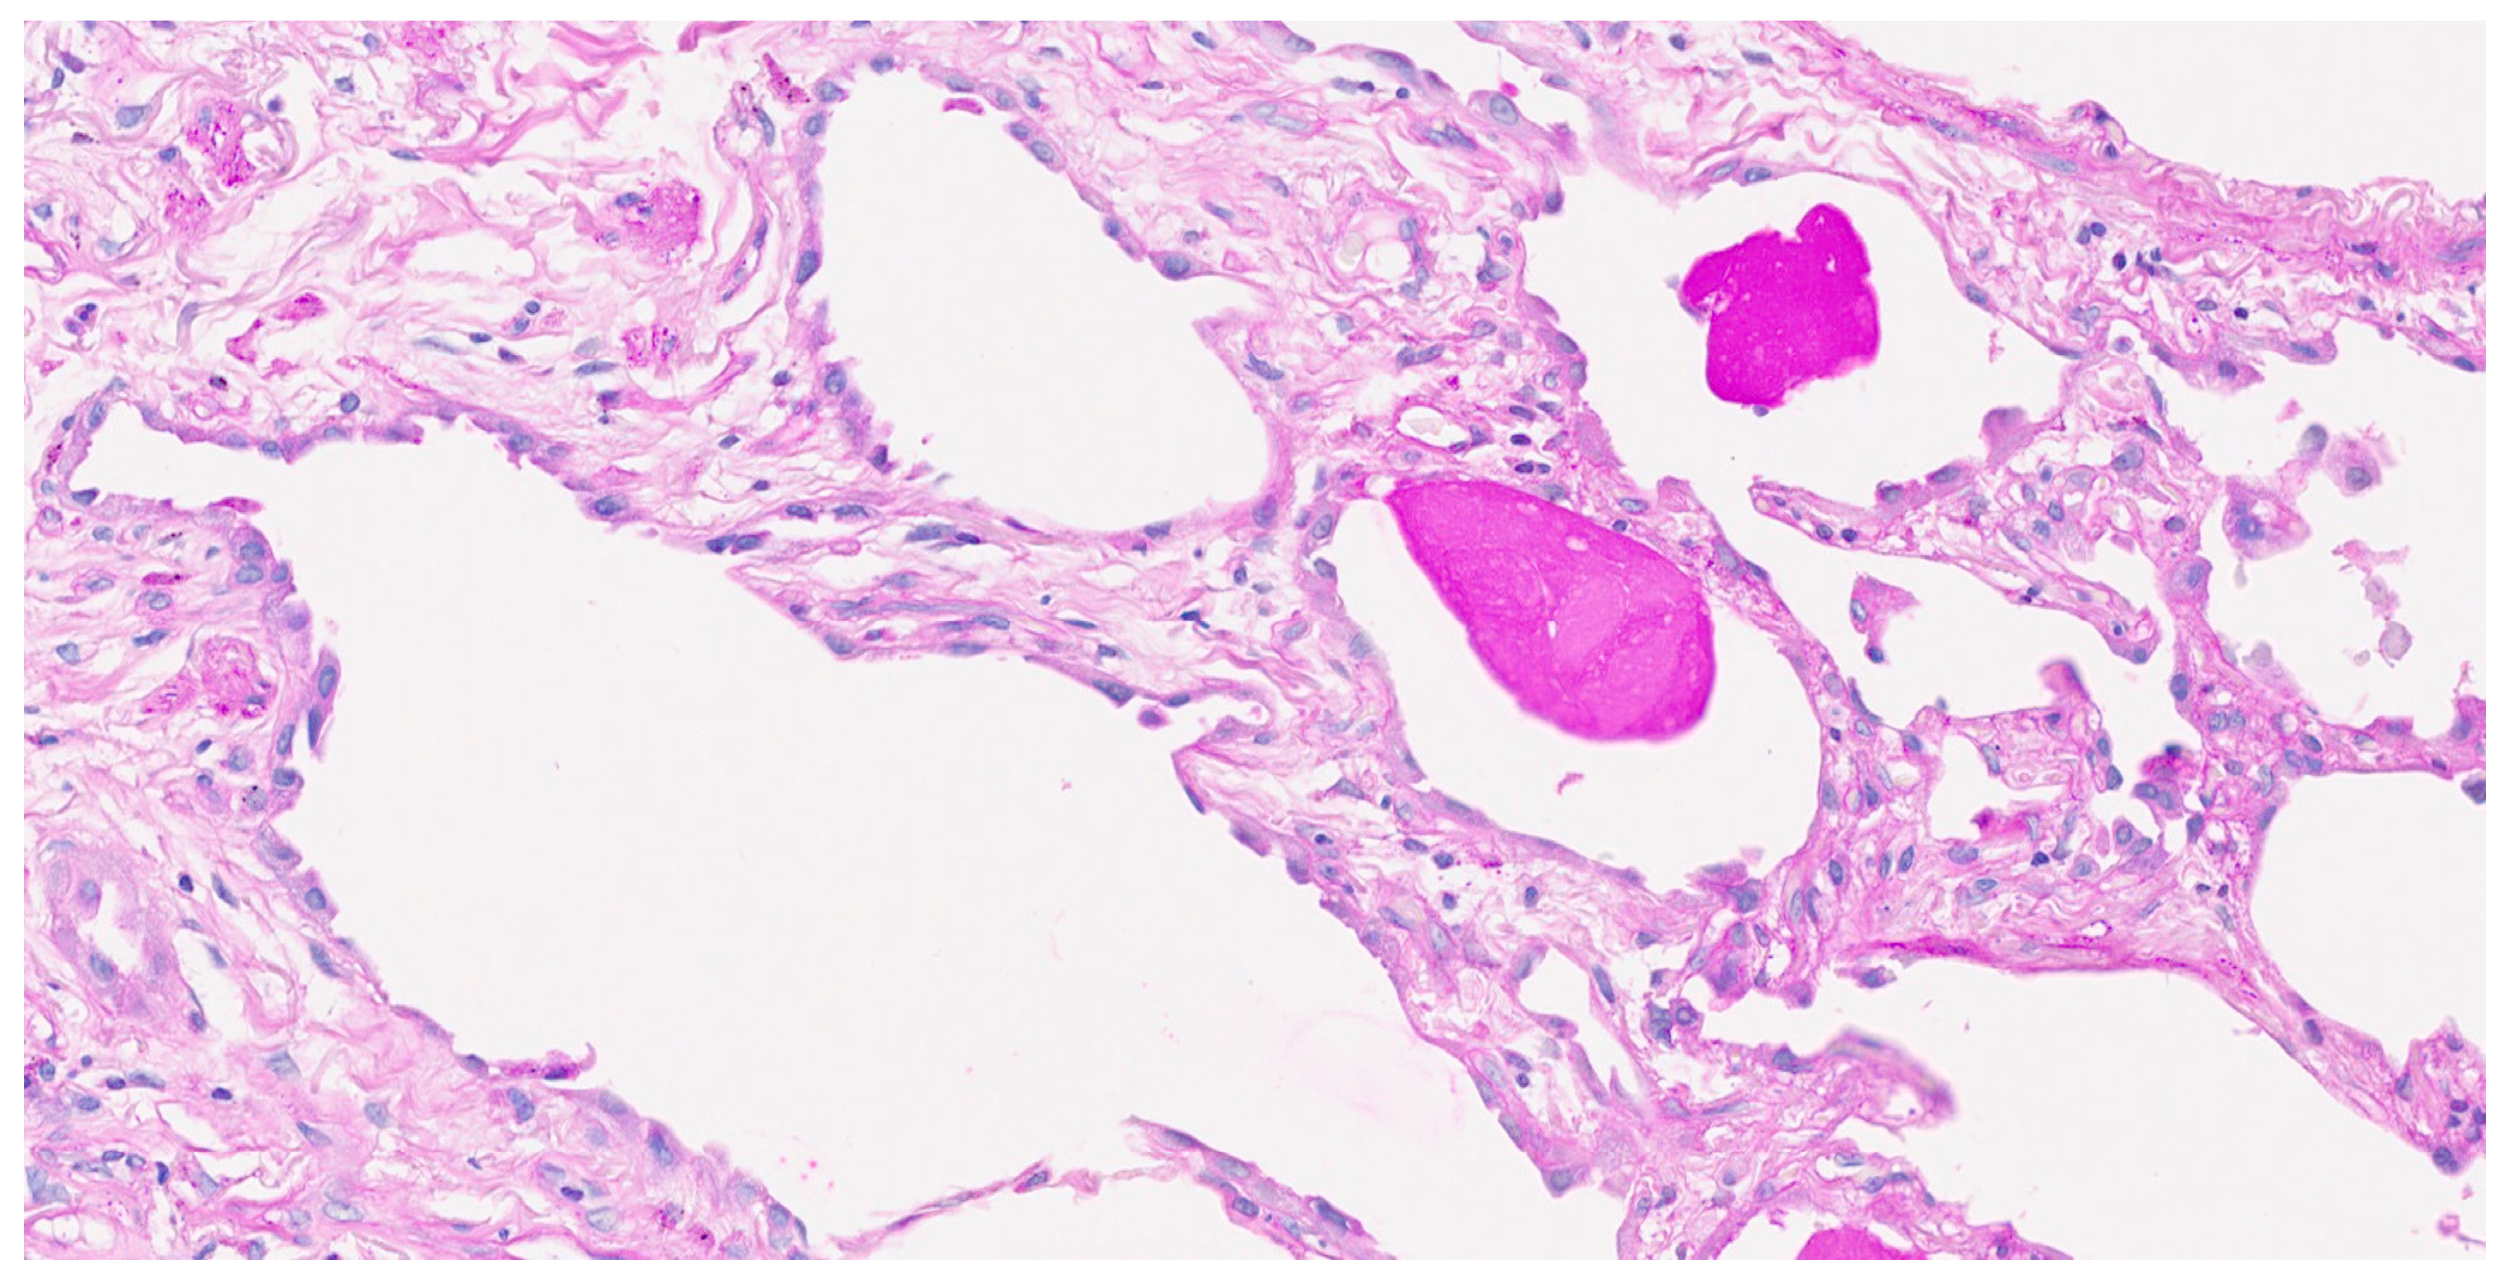

2. Case Report